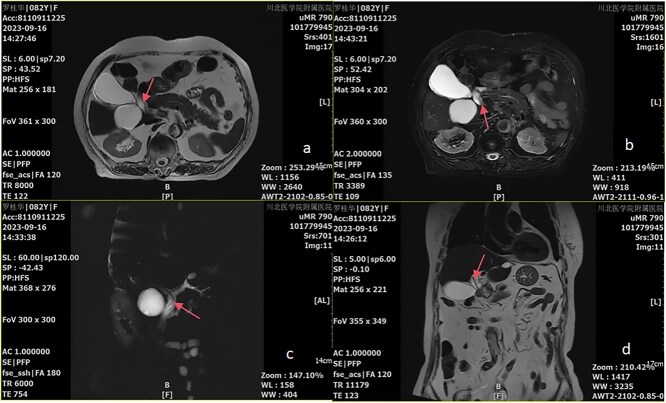

Case presentation: We describe a case of Ascariasis-induced pancreatitis in an 82-year-old woman who was admitted to our emergency department with persistent abdominal pain, nausea, and vomiting for 6 h. Abdominal magnetic resonance imaging and magnetic resonance cholangiopancreatography revealed abnormal tubular signals in the common bile duct segment, accompanied by dilation of the hilar and common bile ducts. Consequently, a diagnosis of Ascariasis-induced pancreatitis was made.